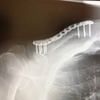

拭き上げたところで、上記の写真。タイヤがすり減ってボサボサした下地が見えてる!!